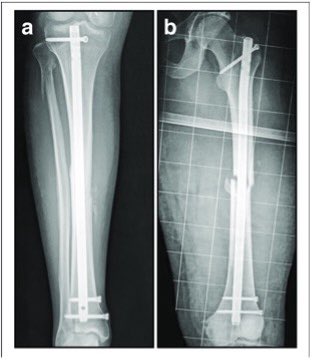

- تركيب مسمار النخاع (Intramedullary nail): يتم إدخال قضيب معدني مصمم خصيصًا في قناة الساق و يمر القضيب عبر الكسر لإبقائه في موضعه مما يساعد على التئام الساق.